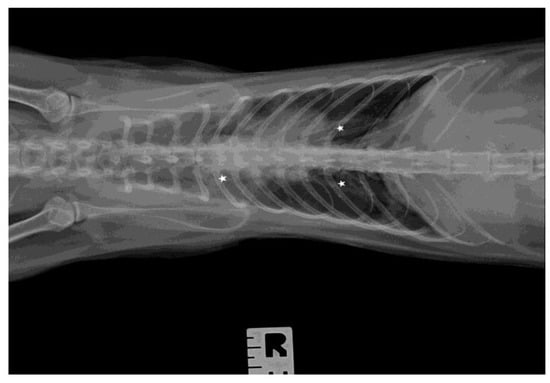

3.3. Ultrasound Examination and X-ray